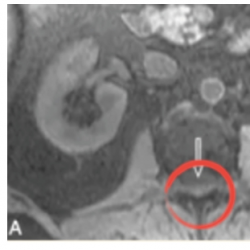

Fig. 4

‘Simple ovarian cyst’ detected in T2 (left) instead of T1 (right).

1). This innovative approach has the potential to yield substantial benefits, including cost savings, time efficiency, and reduced patient discomfort, by eliminating the necessity for multiple MRI scans that require patients to remain motionless for prolonged periods. Moreover, taking the same anatomical structure in a different pulse sequence can assist diagnosticians in detecting underlying pathologies or injuries, such as brain tumours or oedema, as illustrated in Figs.

2,

3, and

4.